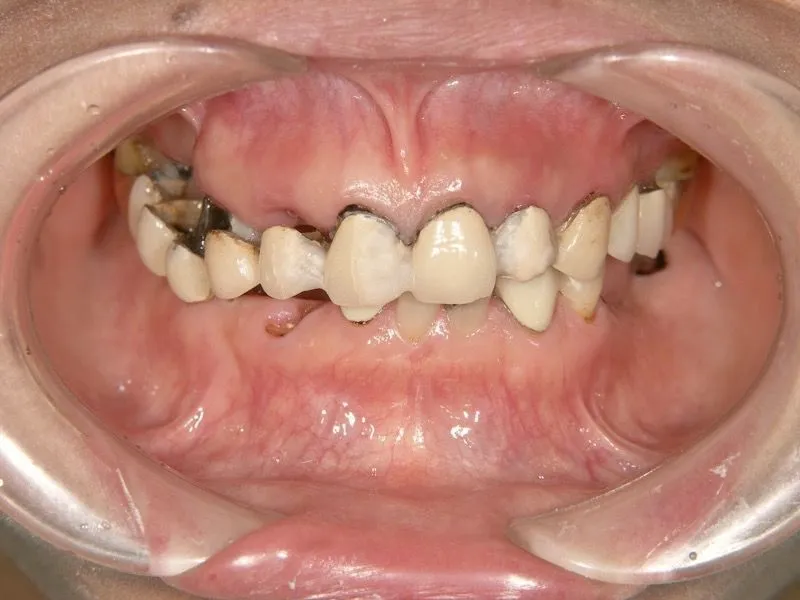

症例

患者様のお悩み | 食事ができない |

|---|---|

治療法・使用素材 | インプラントを用いた全顎的咬合治療 |

患者様の年代 | 40代 |

治療開始年齢 | 49歳 |

治療にかかった期間 | 2年 |

性別 | 女性 |

この治療のリスクについて | |

治療にかかった費用 | 600万 |

治療前